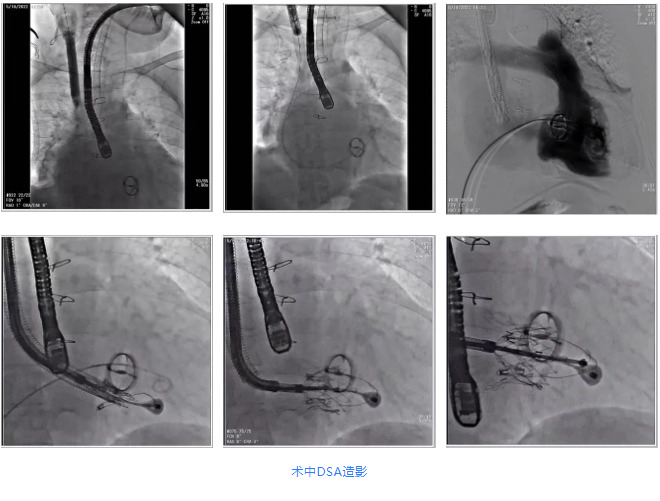

2022年5月18日,四川大學華西醫(yī)院心血管外科郭應強教授團隊,在心內(nèi)科,麻醉手術中心,放射科,心臟超聲等各科室部門全力配合下,成功應用LuX-Valve Plus為一例重度三尖瓣反流患者完成置換手術。團隊前期準備充足,通過術前評估,制定手術策略和預案。術后患者恢復良好,超聲顯示無反流和瓣周漏。此次手術是西部地區(qū)首例經(jīng)血管(頸靜脈)微創(chuàng)三尖瓣置換術(TTVR),也是華西醫(yī)院在探索經(jīng)血管三尖瓣置換領域新的開端,標志著西部地區(qū)結構性心臟病診療邁向新的高度。

根據(jù)術前評估結果,郭應強教授團隊為患者量身定制了手術策略,決定使用LuX-Valve Plus經(jīng)血管三尖瓣置換系統(tǒng)開展手術治療。手術在全麻下進行,采用經(jīng)右側頸靜脈入路,在經(jīng)食道超聲和DSA的指引下調(diào)整輸送器角度以達到正確位置,勾住前瓣后逐步釋放盤片,盤片打開后順利扎針,最終完成瓣膜植入,輸送器撤出。術后超聲提示人工三尖瓣同軸性良好,瓣架固定牢靠,無反流和瓣周漏,術后三尖瓣平均跨瓣壓差為1 mmHg。